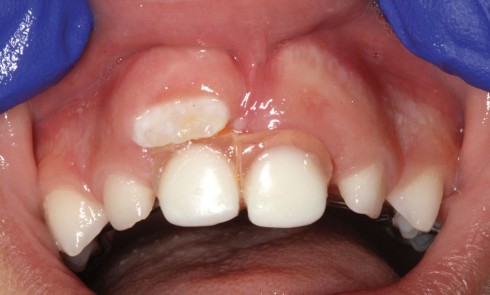

Odontologie pédiatrique

Article réservé à nos abonnés Perte des incisives temporaires maxillaires : faut-il les remplacer ?

La littérature relative à la prise en charge de la perte précoce de dents temporaires est généralement abordée en considérant...